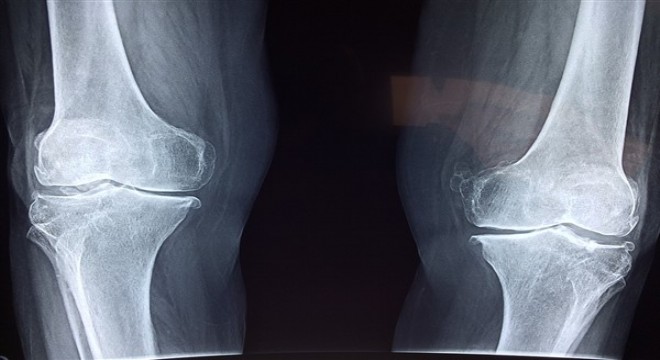

Sigara kullanımı kemik kaynamasını geciktiriyor

Farklı nedenlerden dolayı kırılan kemiklerde kaynamanın gecikmesi veya kaynamanın olmaması, yaş, cinsiyet, beslenme ve yaşam biçimi gibi birçok etkene bağlı olarak gerçekleşiyor. Sigara kullanımının kemik kaynamasını geciktirdiğini vurgulayan uzmanlar, beslenme ve şeker hastalığı gibi faktörlerin de kaynamanın gecikmesinde etkili olduğuna dikkat çekiyor. Uzmanlar, kemik sağlığı için D vitamini açısından zengin olan güneş ışınları ile kalsiyum ve protein açısından zengin yiyeceklerden faydalanılmasını öneriyor.